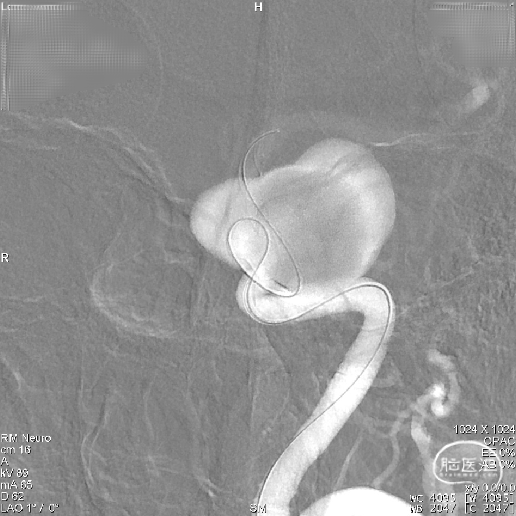

因载瘤动脉较为迂曲,为使支架头端锚定牢固, 4.5mmx45mm Tubridge血流导向密网支架前端1/3处采用稳定支撑系统逐步缓慢给张释放支架,使支架前端充分打开并与血管壁充分贴合。

当Tubridge血流导向密网支架释放到瘤颈弯段位置时,既要保障支架能充分打开、又要保障近端导管张力可控防止支架整体疝入动脉瘤囊内。因此采用节段性“推拉释放技术”既局部给张/松张,来回推挤技术释放支架,并通过持续造影观察支架打开、贴壁及血流转向效果等情况。

通过减影、显影所示,4.5mmx45mm Tubridge血流导向密网支架尾端长度充分且足够,为达到预设计的释放落脚点位置,支架尾端释放采用“推挤+减张瞬间释放技术”通过支架张力使尾端快速打开。

支架打开后即刻造影判断Tubridge血流导向密网支架已充分打开、贴合,同时可见瘤囊内造影剂滞留明显。